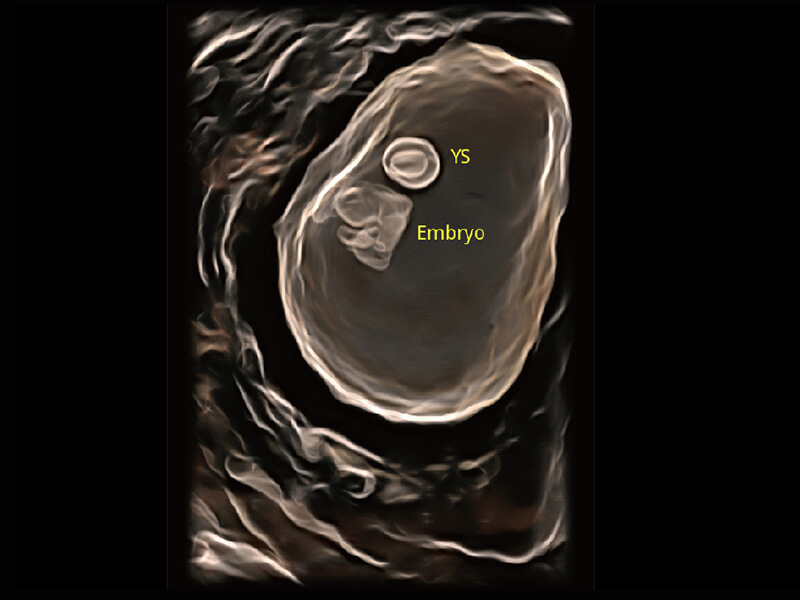

高分辨率容积成像 栩栩如生

超宽频带技术,为容积成像带来优质的二维图像基础,为您呈现丰富的结构细节,栩栩如生地展示宝宝的宫内形态以及各种组织的立体结构。

S-Fetus 产科扫查助手